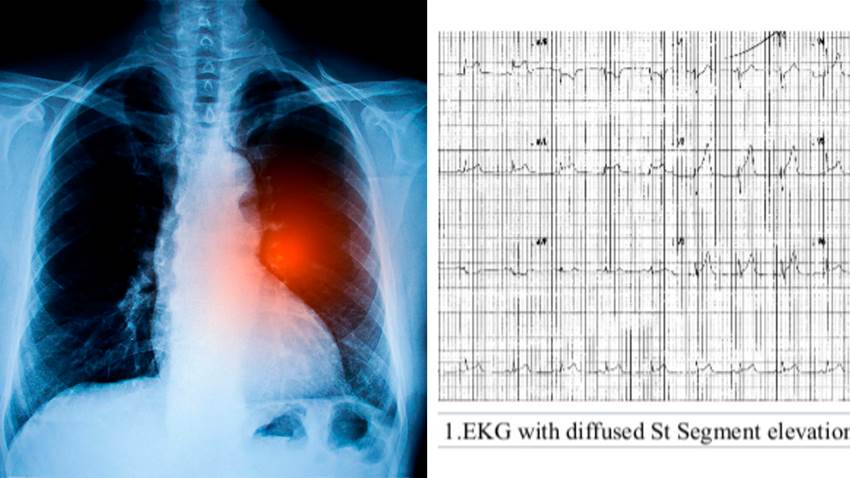

Dolor de pecho en joven de 22 años culmina con diagnóstico de cáncer de pulmón

Un dolor de pecho agudo fue el síntoma alarma de múltiples escenarios clínicos, incluyendo una alta probabilidad que se trate de cáncer, reportado en...